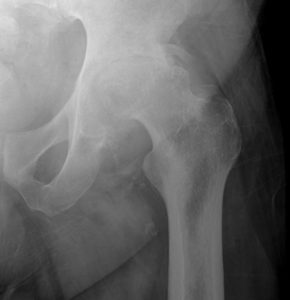

Bone surfaces at joints (such as the hip, knee, or shoulder) are covered by a smooth tissue called cartilage which allows the surfaces to move against each other while providing protection to the bone ends. Arthritis (also called degenerative joint disease) is a condition where this cartilage wears away and changes begin taking place within the joint (figure 1). As cartilage degeneration occurs, pain can develop which can be severe and functional limitations can result.

Note complete obliteration of joint space with deformity.